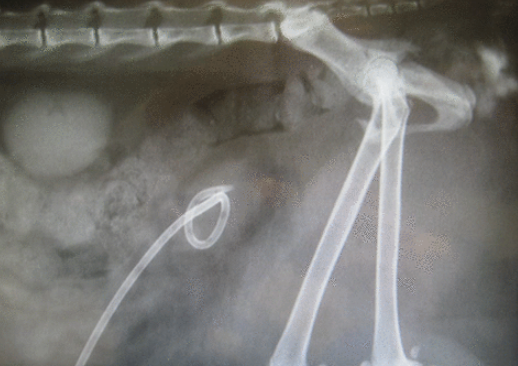

장착을 완료하면

이렇게 장착되게 되고

이런식으로 피부를 통해 방광내 요를 뺄 수도 있다.